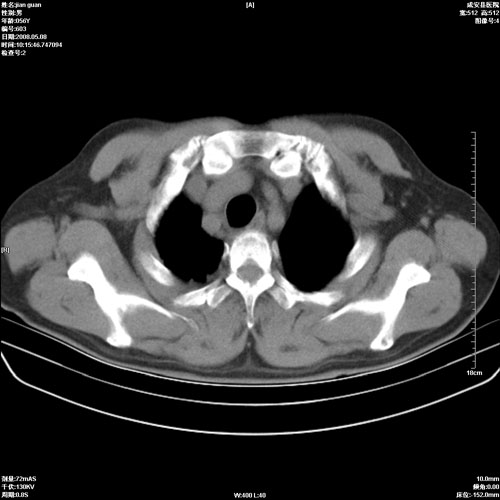

病人 男 60岁 主诉 胸闷 无明显发热 一般情况尚可。

2.心脏增大(以左心室增大为著),请结合b超及听诊.

2.肺门血管扩张,心脏增大,为肺心病

陈旧性肺结核,左心房扩大,左心衰竭